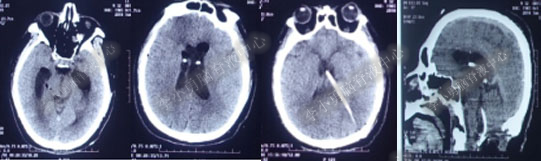

第1次内镜术后330余天即11个月(2017年4月),又开始出现头晕症状并逐渐加重。2017年6月13日(第1次内镜术后367天),行头部MRI(图-4)检查显示全脑室系统扩大。

图-4:2017年6月13日头部MRI

2017年6月19日(第1次内镜术后404天即一年零39天),因原症状加重,第2次住入该院。2017年6月20日(住院第2天),复查头部MRI(图-5)。

图-5:2017年6月20日头部MRI